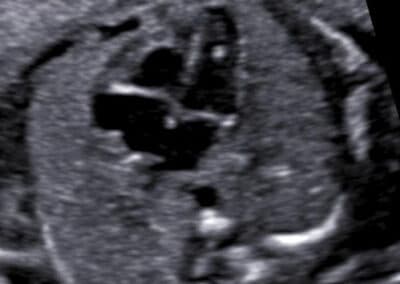

Echogenní fokus v srdíčku miminka, který patří k vyšetřovaným znakům Downova syndromu

Provádíme genetický ultrazvuk dle novějšího modernějšího protokolu s vyšetřením 9 a ne pouze 5 znaků Downova syndromu. Součástí vyšetření je u nás vždy i detailní prohlédnutí srdíčka miminka (fetální echokardiografie), protože srdeční vady doprovází řadu genetických vad a navíc abnormální průběh podklíčkové cévy patří k silným znakům Downova syndromu. Vyšetřujeme drobné detaily a při podezření na výskyt genetické vady si pomáháme i připojením 3D ultrazvuku. Dokážeme tak mnohem přesněji vyšetřit mozek, lebku a vzhled miminka.

Určíme uložení a stav placenty, množství plodové vody a počet cév v pupečníku. Změříme velikost příčného průměru a obvodu hlavičky, obvod bříška a délku stehenní kosti miminka a určíme jeho hmotnost. Vyšetříme také podrobně všechny jeho orgány, hledáme přitom nejen orgánové vady, ale i malých odchylky normálního vzhledu, tzv. markery genetických vad. Pokud si budete přát znát pohlaví miminka, rádi vám jej sdělíme. Při vyšetření mozku miminka, případně lebky a dalších orgánů si pomáháme ke zpřesnění vyšetření i využitím 3D ultrazvuku. Budete-li si přát připojit 3D-4D ultrazvukové vyšetření s reálným zobrazením vzhledu obličeje vašeho miminka , rádi jej také připojíme.